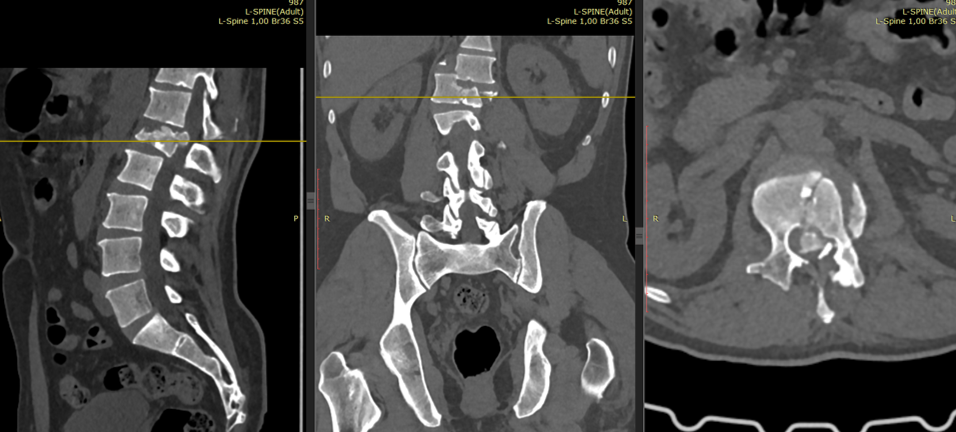

Дообследования выявили комбинацию тяжёлых повреждений позвоночника

Дообследования показали комбинацию тяжёлых повреждений: переломо-вывих Th12 позвонка, взрывной перелом L1 позвонка со смещением в позвоночный канал, сдавление спинного мозга и неврологический дефицит.

Ситуация требовала проведения операции в ранние сроки — и хирургам удалось провести её в первые 12 часов с момента травмы.

Металлическая конструкция установлена в позвоночнике пациента на всю жизнь

Операция проходила утром 5 ноября и длилась около 6 часов. Хирургическая бригада выполнила декомпрессию спинного мозга и редукцию (восстановление взаимоотношений между позвоночными сегментами). Финальным этапом стала транспедикулярная фиксация — ортопеды зафиксировали позвоночник металлической конструкцией с девятью винтами, которая останется у пациента на всю жизнь.